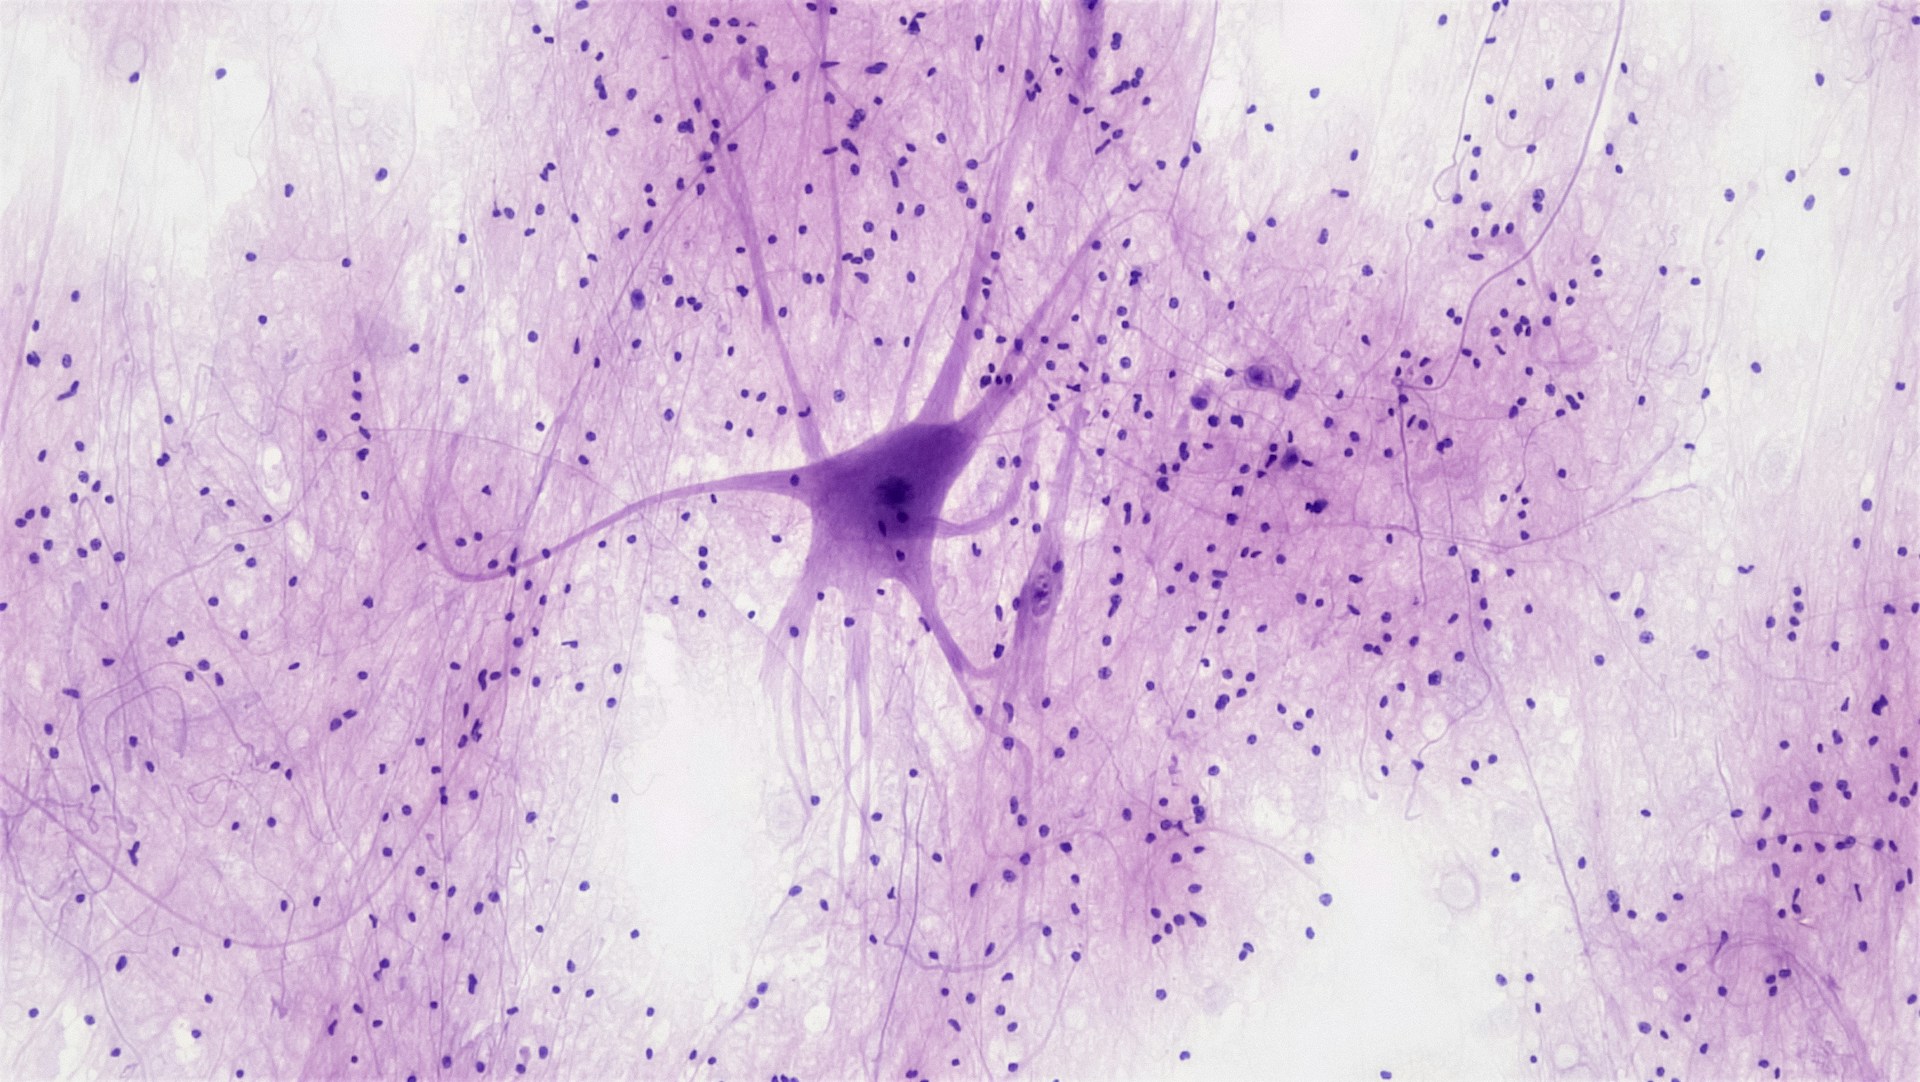

Over the years, the cause of Parkinson’s disease has been somewhat of a mystery for researchers and physicians alike. While many hypotheses of why it develops have been explored, a definitive consensus hasn’t yet been reached. Scientists suspect a range of genetic, environmental, and pharmaceutical aspects may be at the root of the disease, but it’s largely considered idiopathic, where a health condition has no known causes. This is why a new study published in July 2025 has created a stir in scientific circles when scientists discovered a common virus was found in Parkinson’s patients’ brains at high frequency — and not in the control group. What’s more, the virus appears to trigger advanced neuropathological changes, including increased tau pathology, altered levels of certain brain proteins, and differing immune response. Considering Parkinson’s impacts over one million Americans, with approximately 90,000 new cases diagnosed every year, the results of this research are a positive step in understanding — and treating — the disease.

Published in the medical journal JCI Insight, researchers from Northwestern Medicine set out to investigate potential environmental factors such as viruses that may contribute to the development of Parkinson’s.1,2 Using a tool called “ViroFind”, the team analyzed post-mortem brain samples from those with Parkinson’s and individuals who died from other causes. They searched for all known human-infecting viruses in both groups.

The scientists were surprised to find Human Pegivirus (HPgV) in the brains of those with Parkinson’s — but not in those without the disease. HPgV is in the same family as hepatitis C and also a blood-borne virus, but up until now, it was not known to cause any disease.

HPgV is a common, symptomless infection previously not known to frequently infect the brain. “We were surprised to find it in the brains of Parkinson’s patients at such high frequency and not in the controls, “ said Igor Koralnik, MD, chief of Neuroinfectious Diseases and Global Neurology in the Department of Neurology. “Even more unexpected was how the immune system responded differently, depending on a person’s genetics. This suggests it could be an environmental factor that interacts with the body in ways we didn’t realize before. For a virus that was thought to be harmless, these findings suggest it may have important effects in the context of Parkinson’s disease. It may influence how Parkinson’s develops, especially in people with certain genetic backgrounds.”

The team investigated post-mortem brains from 10 people with the disease and 14 without. The virus was found in five of the ten people with Parkinson’s and none of the fourteen control brain samples. It was also discovered in the spinal fluid of those with the disease, but not in the control group.